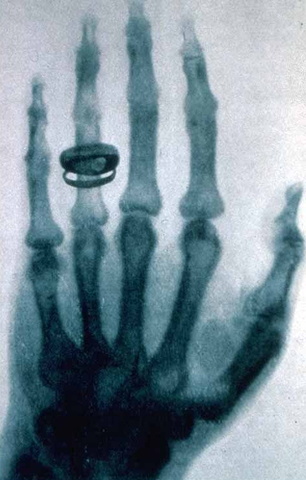

• Primer imagen de rayos X

Primer imagen de rayos X

Realizada en un laboratorio de Física en Dartmourt College por Willhelm Roentgen.